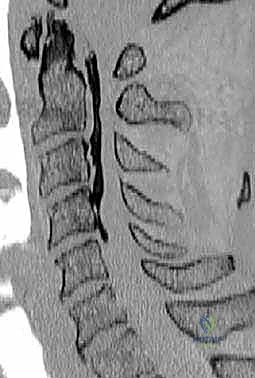

- التصوير بالرنين المغناطيسي (MRI): المعيار الذهبي لرؤية الحبل الشوكي، الأعصاب، والأقراص الغضروفية بوضوح تام، وتحديد مناطق الانضغاط.

- التصوير المقطعي المحوسب (CT Scan): ضروري جداً لتقييم البنية العظمية، التكلسات (مثل OPLL)، والكسور بدقة ثلاثية الأبعاد.

يحدث "تضيق النخاع الشوكي" عندما تضيق هذه القناة العظمية، مما يؤدي إلى خنق الحبل الشوكي. قد يحدث هذا التضيق في مستوى واحد (بين فقرتين) أو يمتد ليشمل عدة مستويات، مما يتطلب إزالة جسم الفقرة بالكامل لتحرير الضغط.